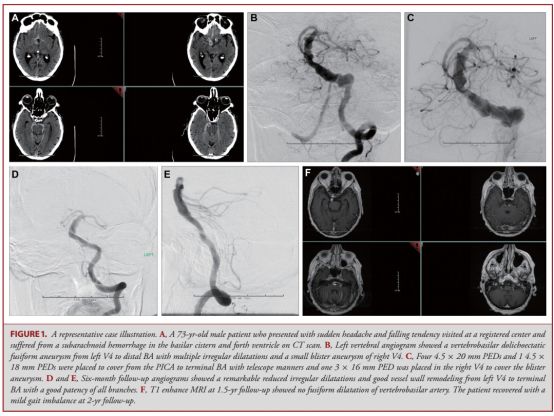

Pineline栓塞装置应用于后循环动脉瘤的安全性仍有争议,本文是基于Pineline的国际性回顾性研究的亚组分析,探讨了使用Pineline治疗后循环动脉瘤的并发症。

研究共纳入2008年7月至2013年2月来自17个医疗中心的91例后循环动脉瘤患者(共95个动脉瘤)。主要终点为并发症引起神经功能症状或死亡。结果发现:所有动脉瘤平均大小为13.8mm,其中囊泡样占36.8%,梭形29.5%,夹层动脉瘤28.4%,其他类型5.3%。随访时间平均21.1个月。12例患者发生终点事件。对终点事件采用多变量分析发现,使用3个及以上PED和梭形动脉瘤有较高的风险比,分别为7.77和3.48。植入PED后动脉瘤大小与神经功能症状的多变量风险比为1.11,而已破裂动脉瘤和年龄与神经功能症状的风险比分别为8.1和1.07。在转归的单变量分析发现基底动脉瘤的风险比为3.54。

作者认为,PED植入是治疗后循环动脉瘤的方法之一,尤其是囊状或夹层动脉瘤。本研究的并发症与之前文献报道的行夹闭和栓塞术后的患者类似。此外,充分考虑动脉瘤的形状、大小、是否破裂、后循环动脉瘤复合体的位置以及年龄、PED植入的等多种因素,有助于帮助神经介入医生做出准确判断。